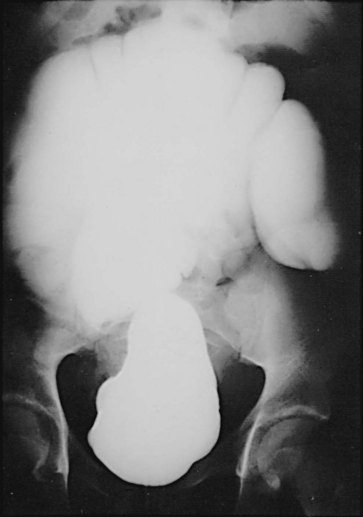

The incidence of intestinal obstruction after abdominal procedures for urinary intestinal diversion differs according to whether the stomach, ileum, or colon is used for the diversion. In patients who have had a segment of stomach or ileum removed for the diversion, there is a 10% incidence of postoperative bowel obstruction requiring treatment. When the colon is used, the incidence of postoperative obstruction requiring an operation is 5% (Table 85–3). Half of the bowel obstructions occur in the early postoperative period. In one series, after radical cystectomy and ileal conduit, 15% of the patients had a mild obstruction in the first 6 months that responded to conservative management, whereas 3% required an operation to relieve the obstruction during this period. The occurrence of obstruction after this 6-month period was much less frequent (Sullivan et al, 1980). More recently, a 10.5% incidence of reoperation for bowel obstruction was noted in a large series of radical cystectomy patients (Varkarakis, 2006). Bowel obstruction can be a morbid event: A significant number of patients who develop obstruction after an ileal conduit and require an operation die. The most common cause of the obstruction is adhesions, followed by recurrent cancer. These two causes account for the great majority of the cases. Volvulus and internal hernia account for far fewer cases (Jaffe et al, 1968). Rarely, severe stenosis or obstruction at the anastomotic suture line occurs. Stenosis is a result of edema, poor technique, or performing the anastomosis on ischemic bowel (Fig. 85–16); obstruction is a result of improper technique.

Intestinal stenosis occurs at two distinct times: in the immediate postoperative period and during the long term. Intestinal stenosis in the immediate postoperative period is due to technical mishaps or edema. Edema resolves by continuing the intestinal decompression, whereas technical mishap requires a reoperation. During the long term, it is likely due to ischemia or perienteric infection. Figure 85–16 shows an upper gastrointestinal tract series of a severe intestinal stenosis caused by ischemia. At the time of the ileoileostomy, the suture line was blue. Chronic symptoms of partial small bowel obstruction occurred in the postoperative period.